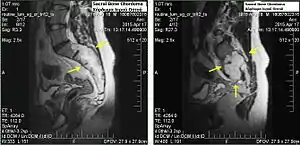

Chordomas can arise from bone in the skull base and anywhere along the spine. The two most common locations are cranially at the clivus and in the sacrum at the bottom of the spine.[2]

In most cases, complete surgical resection followed by radiation therapy offers the best chance of long-term control.[14] Incomplete resection of the primary tumor makes controlling the disease more difficult and increases the odds of recurrence. The decision whether complete or incomplete surgery should be performed primarily depends on the anatomical location of the tumor and its proximity to vital parts of the central nervous system.

In one study, the 10-year tumor free survival rate for sacral chordoma was 46%.[19] Chondroid chordomas appear to have a more indolent clinical course.